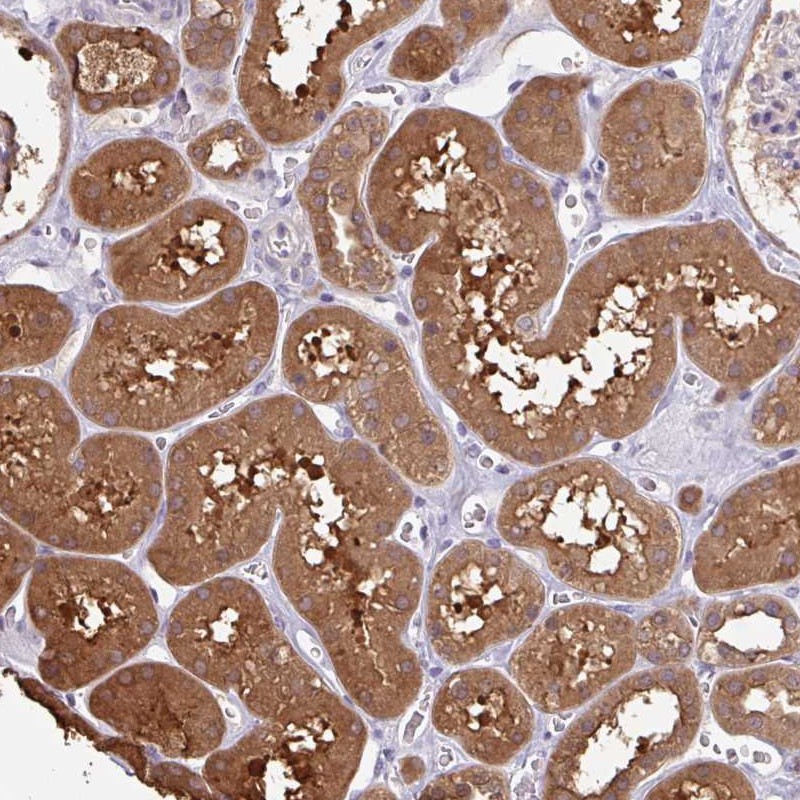

Immunohistochemical staining of human kidney shows strong cytoplasmic positivity in cells in tubules.